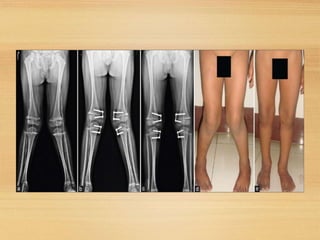

• Guided growth. Thissurgery of the growth plate

stops the growth on the healthy side of the

shinbone which givesthe abnormal side achance

to catch up, straightening the leg with the child’s

natural growth.

• Tibial osteotomy. In this procedure, theshinbone

is cut just below the knee and reshaped to

correct the alignment.

METAPHYSEAL OSTEOTOMY

FOR TIBIA VARA